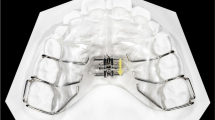

Briefly, the Leaf expander is similar to a conventional rapid palatal expander but instead of being formed medially by a jackscrew, it consists of double nickel-titanium leaf springs (Fig. 1A).

When the leaf springs is activated, it delivers a maximum expansion of 6 or 9 mm, and it generates a constant force of 450 g.

The maxillary expansion protocol for the Leaf Expander was as follows: at the moment of cementation, the device was pre-activated by the laboratory to deliver 3 or 4.5 mm of expansion, after which the re-activation (compressing the leaf springs) was performed by the clinician in the office at subsequent appointments giving the screw activation 10-quarter turns (one-quarter turn corresponds to 0.1 mm) per month until the expansion was achieved.

With regards to the RME protocols, the 10-mm screw of the palatal expander was initially turned two times (0.45-mm initial transversal activation) by the clinician immediately after cementation (Fig. 1B). Afterwards, parents of the patients were instructed to turn the screw twice directly at home per each following day (0.45-mm activation per day). After that, the clinician waited 1 week to reassess the situation and to decide whether to terminate or continue the screw activations in order to obtain a complete expansion.